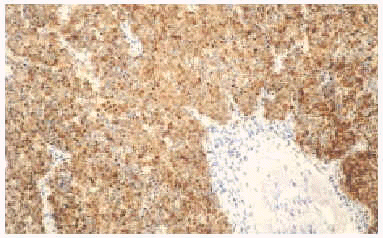

Histológicamente mostraron una disposición dérmica en sábanas o racimos que afectaba a epidermis, en algunos casos. Se registraron 2 casos de invasión linfática. En la mayoría de los casos el tumor estaba formado por pequeñas células basófilas con núcleo redondo y vesicular con cromatina dispersa y nucléolos pequeños periféricos junto con escaso citoplasma (figs. 2 y 3). Las figuras mitóticas fueron en todos los casos muy notables, acompañadas por fenómenos de apoptosis. El estroma presentaba proliferación vascular en forma de fino entramado capilar con endotelios reactivos. En uno de los casos (paciente 2), la histología presentó características peculiares con un patrón epitelioide fusocelular y disposición en trabéculas.

Fig. 2.--Patrón histológico del carcinoma de células de Merkel.

Fig. 3.--Patrón histológico del carcinoma de células de Merkel (HE, x200).